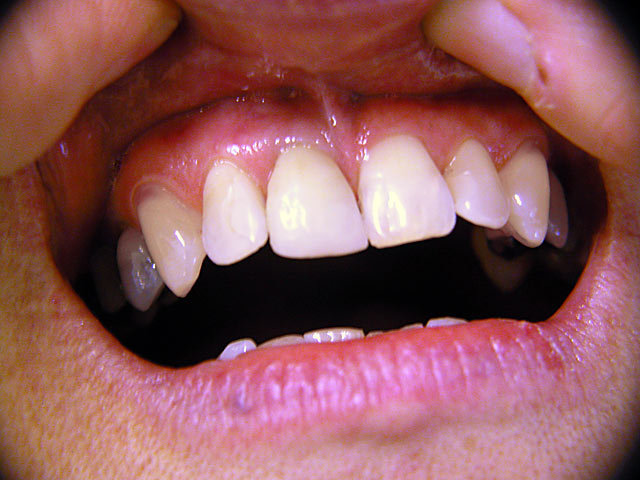

Frontzahn-Implantation: